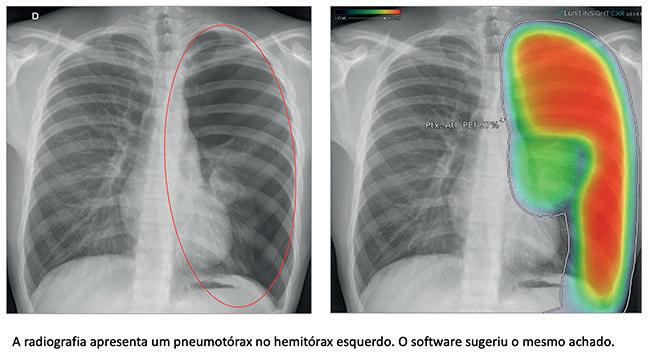

Además de las infecciones pulmonares, la herramienta es capaz de detectar otras patologías en el tórax, especialmente nódulos pulmonares (incluidos pequeños tumores), derrame pleural (acumulación de líquido alrededor de los pulmones), neumotórax (cuando se acumula aire alrededor de los pulmones, por ejemplo, tras la rotura de una burbuja pulmonar), cicatrices pulmonares (secuelas infecciosas) y agrandamiento del corazón. Dado que se diseñó para ser una herramienta de apoyo a los médicos en la interpretación de imágenes radiográficas, el algoritmo de IA es bastante sensible, es decir, se diseñó para no dejar pasar desapercibidos cambios potencialmente importantes. Debido a ello, pueden producirse algunos resultados falsos positivos (por ejemplo, “nódulos pulmonares” artefactuales -no reales-), por lo que es fundamental una evaluación médica paralela a la herramienta. Los resultados falsos negativos son más raros, precisamente por la alta sensibilidad del algoritmo, pero también pueden ocurrir, estando mucho más relacionados con las limitaciones del método que con la propia herramienta; sólo como ejemplo, las llamadas opacidades en vidrio deslustrado, que han ganado notoriedad en el escenario Covid-19 (cuando indican inflamación/infección pulmonar), pueden ser difíciles de detectar en la radiografía de tórax, incluso con el apoyo del algoritmo de IA.

En el contexto en el que lo estamos utilizando, los pacientes rara vez se derivaban para punciones. Así pues, creemos que el mayor beneficio será evitar que los pacientes que tienen un nódulo, una neumonía o un neumotórax se queden sin un seguimiento adecuado.